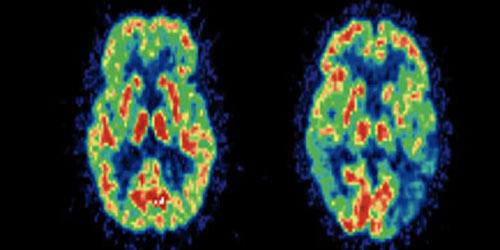

Áøº¸¿Í º¸¼ö´Â ³ú±¸Á¶°¡ ´Ù¸£´Ù´Â ¿¬±¸ °á°ú

Àç¹ÌÀÖ´Â ¿¬±¸ °á°ú°¡ ³ª¿Ô´Âµ¥, ÀÚ½ÅÀÇ Á¤Ä¡Àû ¼ºÇâÀ» ¡®Áøº¸¡¯¶ó°í ¹àÈù »ç¶÷µéÀÇ ³ú´Â »ç¹°À» ÀÌÇØÇÏ°í º¹ÀâÇÑ Ãß»óÀû °ü³äµéÀ» °áÇÕÇØ ƯÁ¤ÇÑ »ç»óÀ¸·Î ¸¸µå´Â ´É·ÂÀ» °üÀåÇÏ´Â °÷ÀÌ ¹ß´ÞÇß°í, ¹Ý¸é ½º½º·Î¸¦ ¡®º¸¼ö¡¯¶ó°í ¹àÈù »ç¶÷µéÀÇ ³ú´Â ¹«¼­¿ò°ú °øÆ÷, °ÆÁ¤, ºÒ¾È µûÀ§¸¦ °üÀåÇÏ´Â ¶¥Äá ¸ð¾çÀÇ ºÎºÐÀÌ ¹ß´ÞÇØ ÀÖ¾ú´Ù´Â °ÍÀÌ´Ù.

"¡®Áøº¸¡¯ÀÇ ³ú´Â ³ôÀº ÀÌÇØ·Â°ú »ç°í ´É·ÂÀ» Áö´Ô°ú µ¿½Ã¿¡ ¼Ò³úÀÇ ºÒ¾È °üÀå ºÎºÐÀÌ ÀÛ¾Æ Áö±Ý ÇöÀç ÇØ°áÀÌ ºÒ°¡´ÉÇØ º¸ÀÌ´Â »çȸÀû ¹®Á¦µéµµ »õ·Î¿î ÇØ°áÁ¡À» ãÀ» ¼ö ÀÖ´Ù´Â ½ÄÀ¸·Î ³«°üÀû ¹Ì·¡°üÀ» Áö´Ï°Ô µÇ´Â °ÍÀ¸·Î ÇØ¼®ÇÒ ¼ö ÀÖ´Ù°í ¿¬±¸ÆÀÀº ¼³¸íÇß´Ù. ÀÌ¿¡ ºñÇØ ¡®º¸¼ö¡¯´Â ÀÌÇØ·ÂÀ» °üÀåÇÏ´Â ºÎºÐº¸´Ù ºÒ¾È°ú °øÆ÷½ÉÀ» °üÀåÇÏ´Â °¨Á¤ ºÎºÐÀÌ ¹ß´ÞÇØ ÇöÀ縦 ¹Ù²Ù°Ú´Ù´Â ¸ðÇèÀ» ½±°Ô °¨ÇàÇÏÁö ¸øÇÒ »Ó ¾Æ´Ï¶ó ³²µéÀÌ À̰°Àº ¸ðÇèÀ» ÇàÇÏ´Â °Íµµ ¸·°Ô µÈ´Ù´Â °ÍÀÌ´Ù."